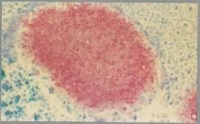

病原体从伤口进入皮下之后,经过较长的潜伏期,在原外伤部位出现皮下结节结节增大、变软、破溃,排出脓液,脓液中含有小米粒大小或更小的不同色泽的颗粒,一般为圆形,颗粒由真菌或放线菌的菌丝团块组成,外面包绕一层嗜酸性染色物质,可能是抗原抗体复合物抗真菌药不易透入。小的颗粒还可被淋巴带到其他部位,病原体在该处继续生长繁殖,造成在皮损周围发生多数类似的结节,可互相融合。皮损有很深的瘘管。皮损增多,患部肿大变形。损害可侵入深部组织达到骨骼,引起骨质破坏骨质增生,形成一个肿胀假性肿瘤样改变。